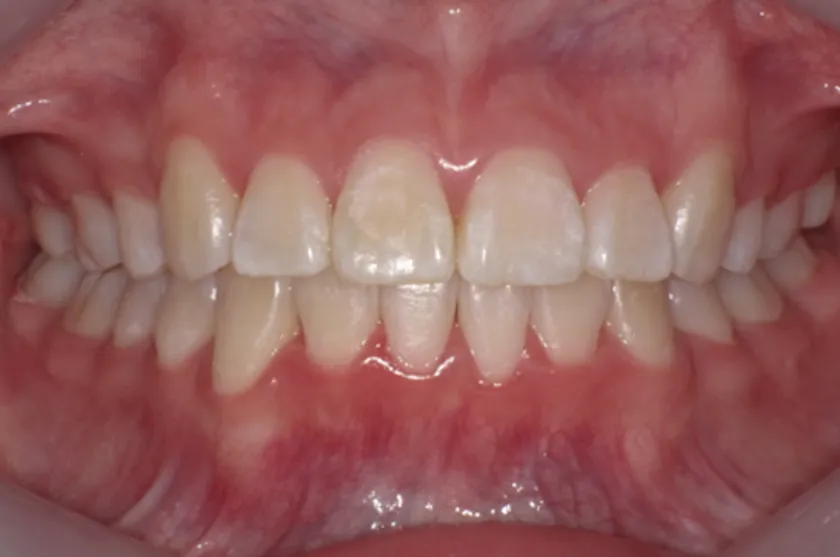

前歯部のトルクコントロール、上下顎の正中の一致、犬歯関係、大臼歯関係が良好になり、咬合関係が改善。(写真c)

c:7か月後